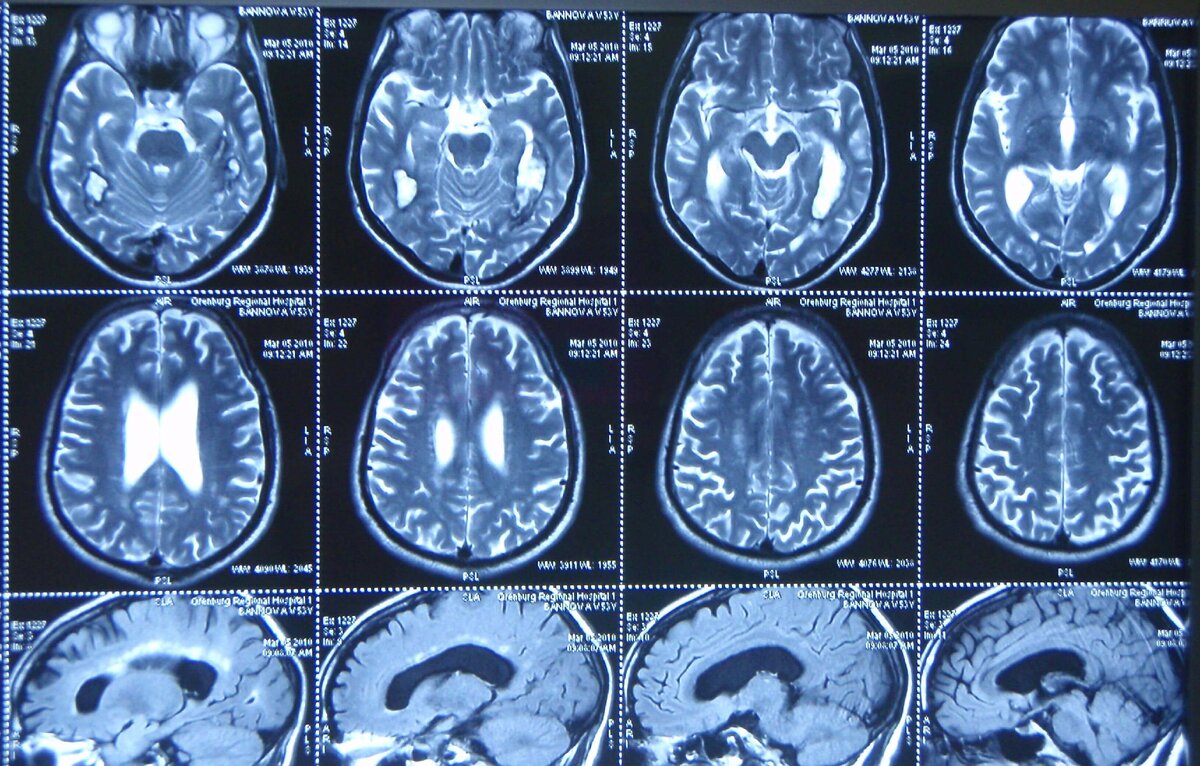

Найден ген, который защищает людей от развития болезни Альцгеймера

Ученым удалось выяснить, что наличие данного гена в организме защищает его от развития болезни или снижения скорости развития нейродегенерации. В исследовании, проводимом международной группой ученой, участвовали дети с синдромом Дауна. Есть мнение, что в семидесяти процентах случае именно у таких детей развивается нейродегенеративное отклонение. Специалистам удалось выяснить, что ген BACE2 функционирует практически так же, как гены-супрессоры опухолей. Выяснилось, что при повышении активности данного гена развитие болезни Альцгеймера начинало замедляться или полностью предотвращалось. Той же группе ученых удалось создать платформу для быстрого диагностирования нейредегенативных изменений. Существующие платформы работают только в том случае, когда у пациента наблюдаются нарушения, свойственные заболеванию. Для диагностики берутся клетки человека, а в последствии преобразуются в стволовые клетки. Далее их опять же преобразуют в клетки головного мозга и начинают наблюдение за